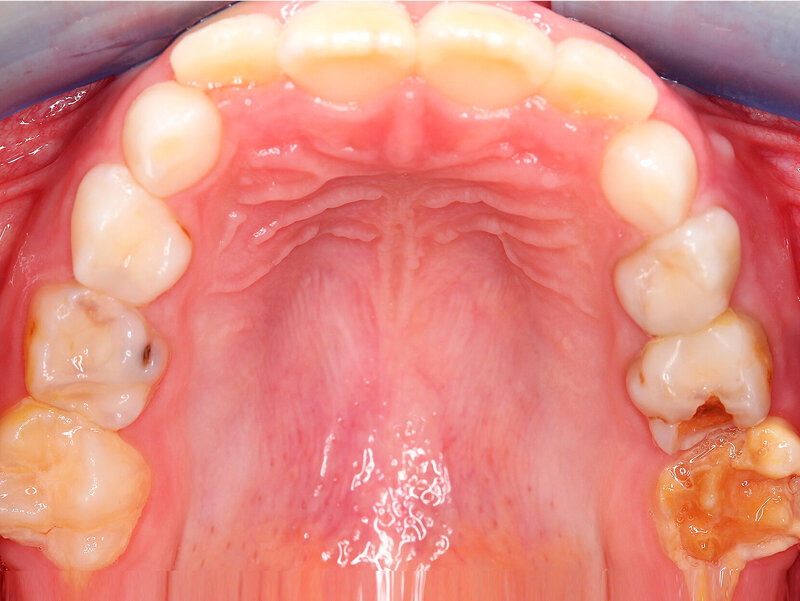

Die Ausprägung der Mindermineralisation kann stark variieren (Abbildungen 3 und 4). Klinisch zeigen sich an den betroffenen Zähnen unterschiedlich starke Verfärbungen beziehungsweise Opazitäten bis hin zu ausgeprägten Schmelzverlusten. So kann die Mineralisationsstörung im Bereich der Molaren auf einzelne Bereiche beschränkt sein, das Fissurenrelief einbeziehen oder sich über die gesamte Glattfläche erstrecken [Koch et al., 1987]. Bei den Inzisiven ist die Mindermineralisation bukkal zu finden. Geringgradig betroffene Zähne sind dabei eher durch weiß-gelbliche oder gelb-braune, unregelmäßige Verfärbungen gekennzeichnet, schwere Hypomineralisationsformen weisen dagegen abgesplitterte oder fehlende Schmelz- und/oder Dentinareale unterschiedlichen Ausmaßes auf.

Sind bei einem Patienten mehrere Molaren betroffen, so kann es auch hier zu Variationen kommen. Dementsprechend kann es sein, dass bei einem Molaren kleine, intakte Opazitäten zu finden sind, während an einem anderen Molaren große Teile des Schmelzes bereits kurz nach dessen Eruption einbrechen [Weerheijm, 2004].

Bildgruppe Abb. 7–14:Grade des MIH-Treatment-Need-Index im klinischen Erscheinungsbild